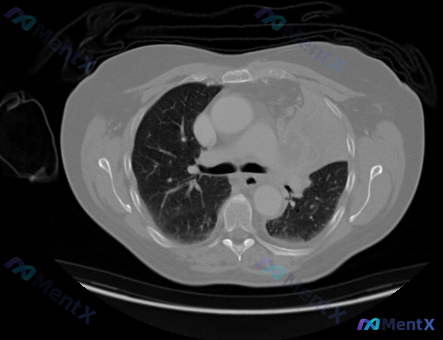

最近看到一个很典型的影像读片场景,整理一下思路和大家分享。 病例背景 有医生发来一张单幅的胸部CT横断面(肺窗),直接问:“帮我确定一下这张照片里的癌症分期。” 先看影像客观表现 根据影像分析: - 肺实质:双肺纹理走行清晰,分布均匀;未见明显磨玻璃影(GGO)、实性结节、肿块或斑片状实变影;肺野透...

整理了一个很有意思的读片案例,不是那种“一眼诊断”的典型图,但非常考验临床思维——因为问题直接预设了“癌症”,但影像本身却很“干净”。 先看影像情况(客观描述) 这是一张胸部CT纵隔窗横断面: - 纵隔淋巴结:隆突下、双侧肺门、气管旁及主动脉弓周围,都没见明显肿大的淋巴结,间隙也很清晰。 - 大血管...

今天看到一个影像分析需求挺有意思:拿到一张胸部CT(纵隔窗,主动脉弓层面),要求直接「识别具体癌症类型,包括位置、大小、淋巴结受累、转移状态和分期」。 先整理下这份影像的核心观察结果: - 纵隔淋巴结:气管旁、腔静脉后等区域脂肪间隙清晰,未见明显肿大; - 大血管与心脏:主动脉弓、肺动脉、上腔静脉走...